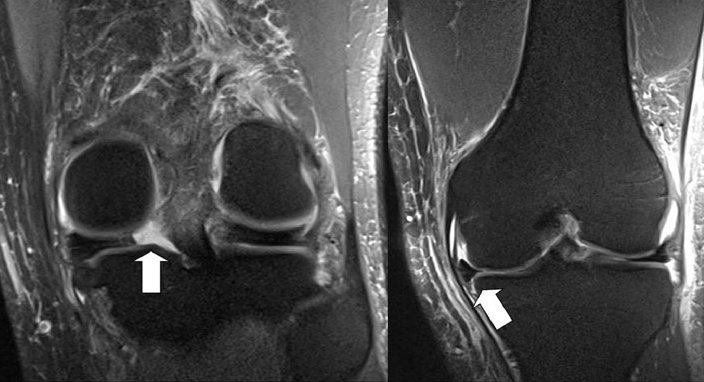

If you have a knee problem, in most situations I believe it will be helpful for you to have such an MRI scan of your knee - to make or support a diagnosis or to exclude other reasons for your problem. MRI scans are particularly useful in the evaluation of meniscus tears, and tears of the anterior cruciate ligament (ACL) and other ligaments. If your main problem is knee pain I believe you should in most circumstances as part of the investigation have an MRI scan of the knee, and indeed I feel you should not have an arthroscopy unless you have had an MRI evaluation. The price has declined considerably over recent years, making MRI a much more affordable aid to diagnosis, and today a knee MRI is close to 400 euros in Denmark (where I practice).